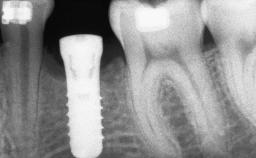

A 47-year-old woman who had suffered from aggressive periodontitis requiring a number of periodontal interventions over more than 10 years was referred by her general dental practitioner and periodontologist for bone augmentation and implant therapy. Her failing dentition had already been scheduled for extraction. The patient expressed a desire for implant-supported fixed restorations and esthetic improvement of her lower face. She had agreed to consult with a maxillofacial surgeon after the referring dentist had suggested bone augmentation. An initial examination by the maxillofacial surgeon revealed mobility of all residual teeth in a patient who was very unhappy with the function of her removable partial dentures. Due to periodontally migrated flaring teeth and loss of occlusal support, the vertical dimension of occlusion was dramatically reduced. The patient was displeased with her lower face because of deepened nasolabial, commissural, and supramental folds.

# of Implants 14

Type of Implants Two-Piece